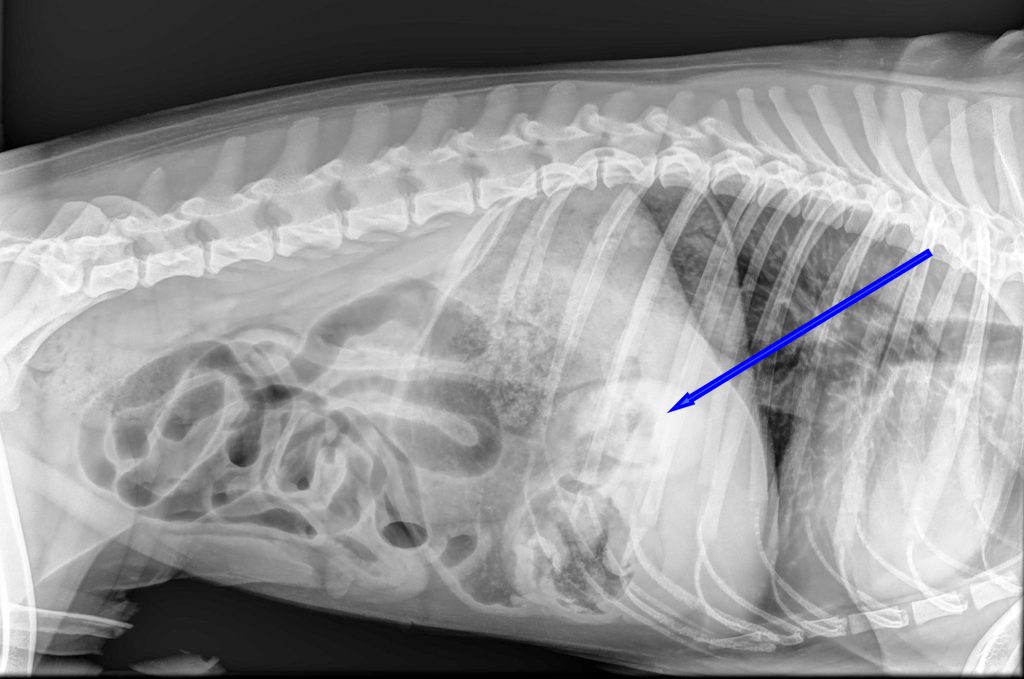

Bij het algemeen onderzoek was de buik gevoelig bij het navoelen en er leek veel gasvorming aanwezig te zijn. Op de röntgenfoto was er een grote maag met veel vulling zichtbaar, waarbij er ook een soort buisvormige structuur aanwezig leek te zijn. Het leek er dus op dat er een vreemd voorwerp in de maag zat. Aangezien Joep al meerdere keren had gebraakt zonder dat er iets uit kwam, was het advies om dit voorwerp operatief te verwijderen.